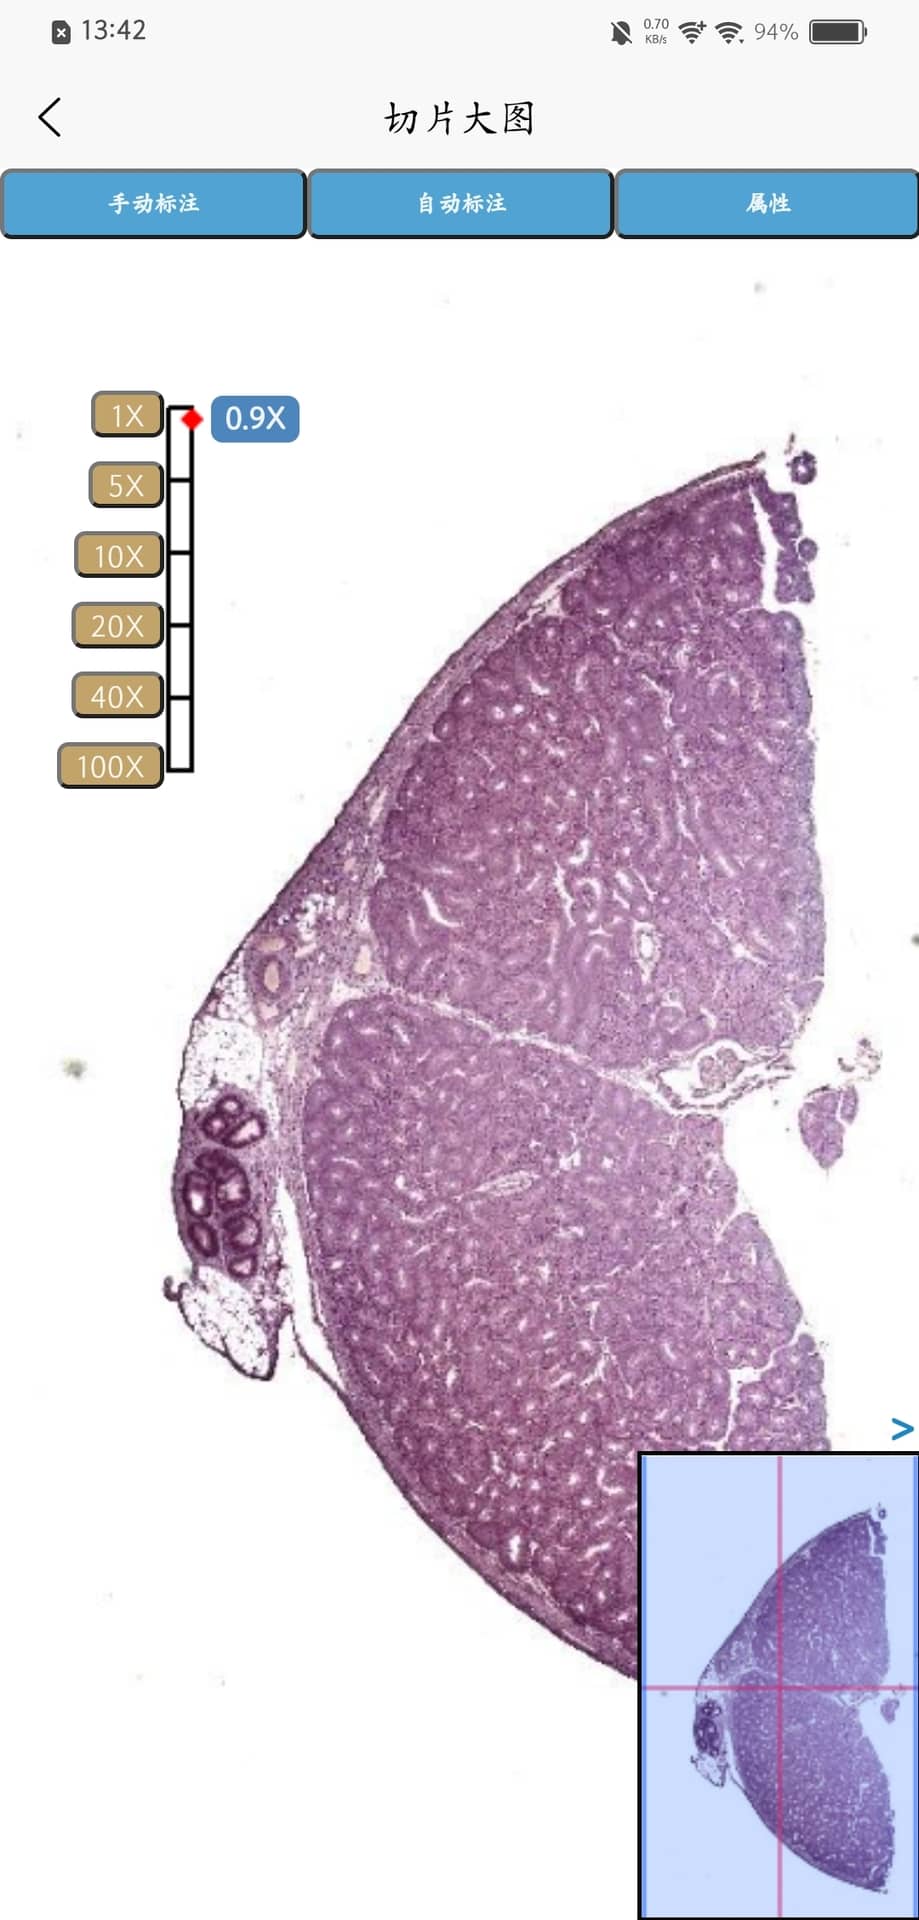

Turingene 是一款由苏州迪美格智能科技有限公司开发的手机应用,专为病理切片扫描提供便利。用户只需使用该 App 对病理切片进行扫描,即可生成可共享的数字切片文件。这些数字切片能够帮助病理医生更高效地进行病情诊断,并方便地与其他医师进行远程协商。

Turingene是一款由苏州迪美格智能科技有限公司自主研发的App,用户可以通过此App,进行病理切片的扫描,扫描完成的切片可以进行内外部分享,协助病理医生病情诊断